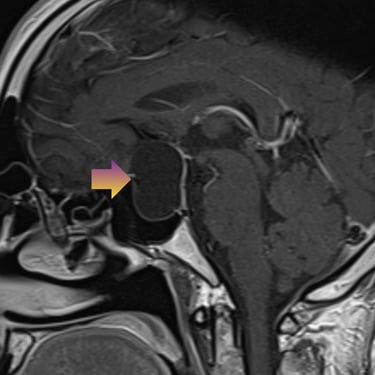

🧠Tumor selar quístico: abordaje mediante cirugía endoscópica transnasal (endoscopía selar).

Los tumores selares quísticos, como los adenomas hipofisarios quísticos o quistes de la bolsa de Rathke, pueden generar alteraciones visuales y hormonales. La cirugía endoscópica transnasal es una técnica mínimamente invasiva que permite el acceso seguro a la región selar, favoreciendo una resección eficaz con menor morbilidad.